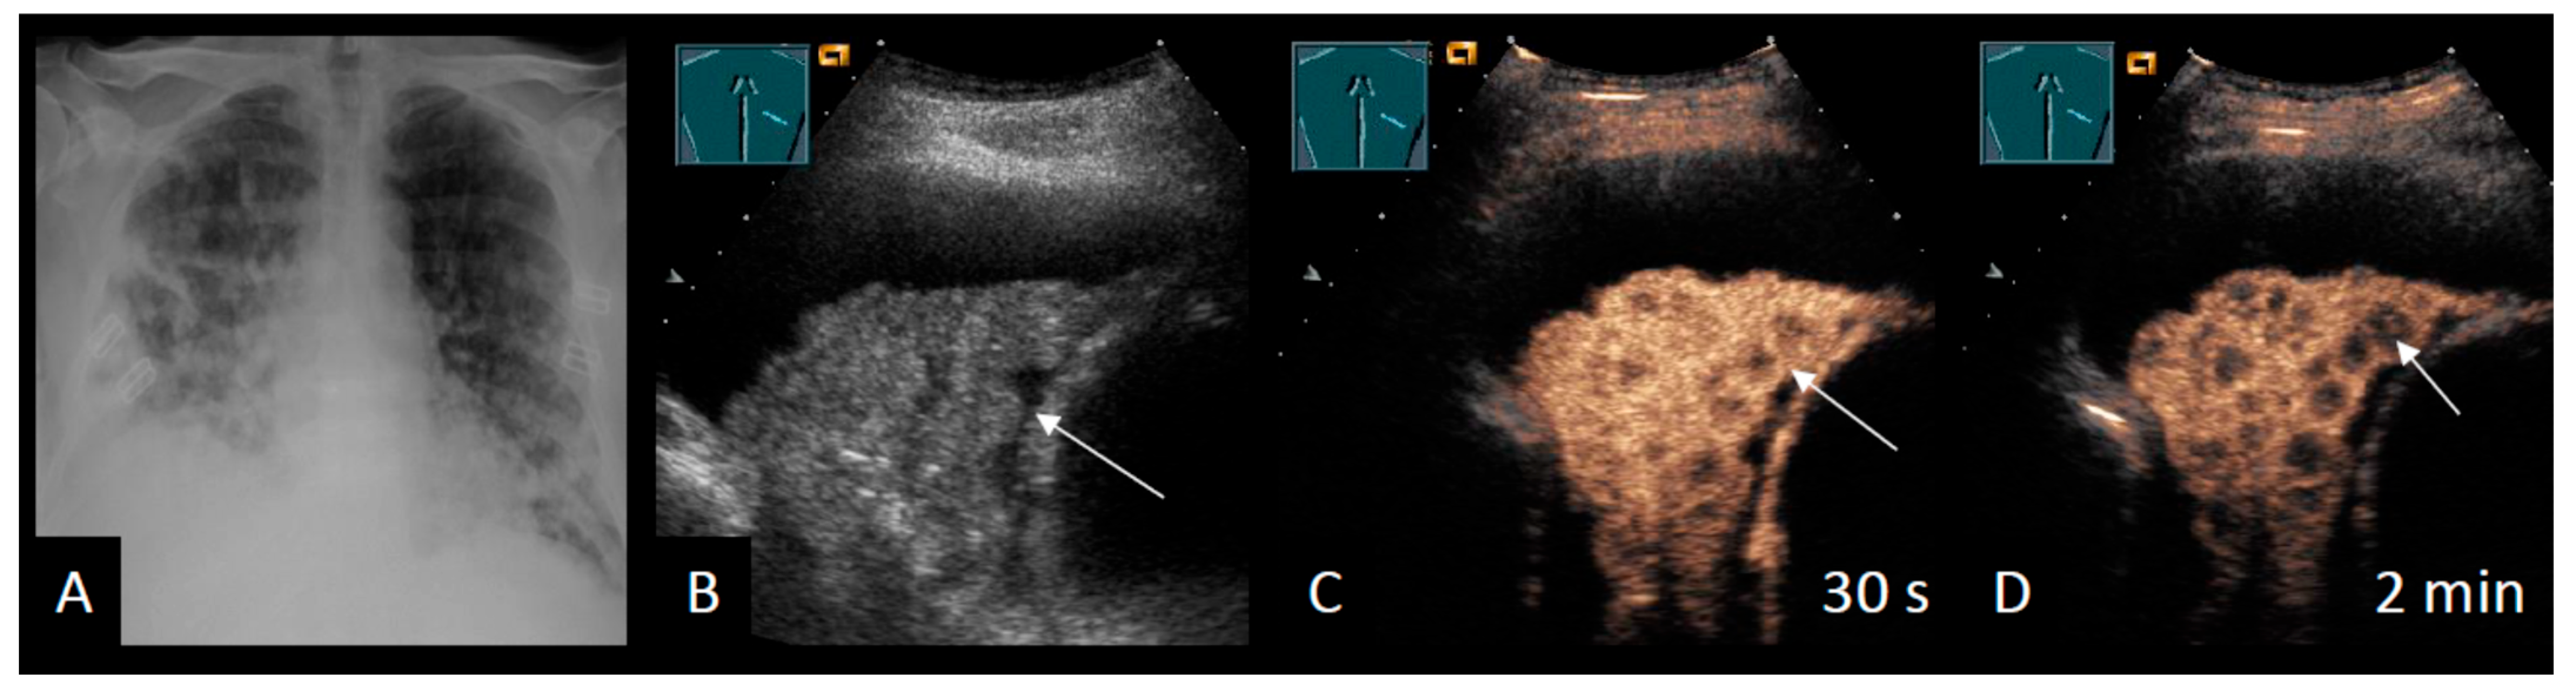

2.4. Intrapulmonary Lesions

Additional Ultrasound Techniques

| CEUS | ||||

| Safai Zadeh et al. [53] | 2021 | n = 83, single-center, retrospective study | To evaluate the value of CEUS in differentiating malignant from benign PE | Sensitivity B-mode: 69.1% Specificity B-mode: 58.5% Sensitivity CEUS: 73.8% Specificity CEUS: 70.7% Subgroup (cytological negative, high risk for MPE): Sensitivity CEUS: 92.3% Specificity CEUS: 90.0% |

| Findeisen et al. [56] | 2022 | n = 63, single-center, retrospective study | To describe the value of CEUS for the differentiation of malignant from benign parietal pleural lesions (Pleural effusion in 50.8%) | Sensitivity CEUS: 92% Specificity CEUS: 54% |

| Yang et al. [58] | 2022 | n = 50, single-center, prospective study | To investigate the diagnostic capabilities of B-mode LUS and CEUS in terms of differentiating between benign and malignant pleural diseases | Multivariate logistic regression: Sensitivity 93.3% Specificity 90.0% |